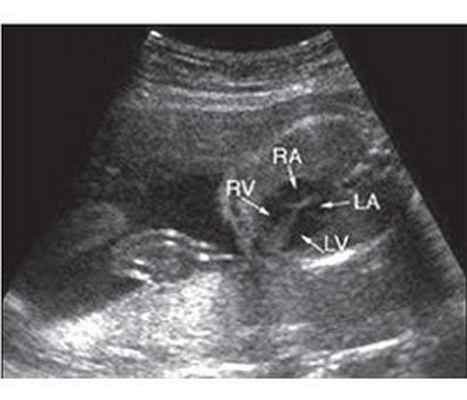

На ЭхоКГ: сужение на уровне клапанов или под-клапанного пространства (рис. 2, 3), гипертрофия миокарда передней стенки правого желудочка и межжелудочковой перегородки, увеличение полости правого предсердия и др.

Рисунок 2. Стеноз легочной артерии. Новорожденный первых часов жизни. Сканирование путей оттока из правого желудочка (&УОТ). Отмечается критический стеноз на уровне клапанов легочной артерии (РА), створки клапана фиброзно изменены (стрелка); АО — аорта

Рисунок 3. ЭхоКГ: сужение на уровне клапанов и подклапанного пространства

На ЭхоКГ: сужение на уровне клапанов или подклапанного пространства (рис. 2, 3), гипертрофия миокарда передней стенки правого желудочка и межжелудочковой перегородки, увеличение полости правого предсердия и др.